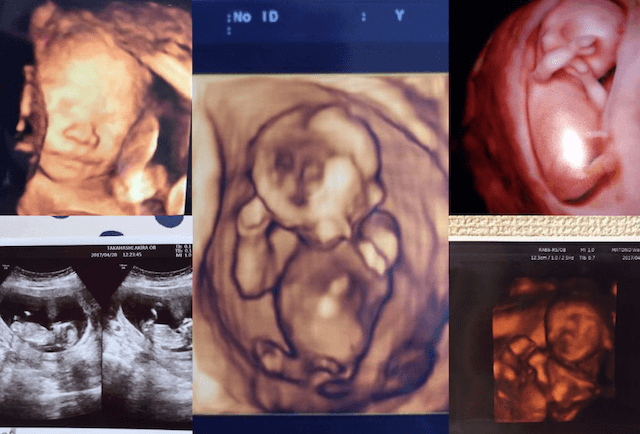

たくさんのご応募ありがとうございました!

400通を超えるお写真をいただきました!

どのエコー写真も本当にママパパ、ご家族の思い出が詰まっているものでした。女の子、男の子だと性別が判明したエコー写真、双子だとわかってびっくりしたエコー写真、喧嘩の仲直りのきっかけになったエコー写真、おもしろポーズで家族の笑顔を生み出したエコー写真などまだまだ紹介したいものばかりです。

今回受賞された方以外のエコー写真もコズレの記事内でご紹介させていただく予定です!ぜひ隅々まで記事をご覧いただきお子さんのお写真探してみてくださいね!